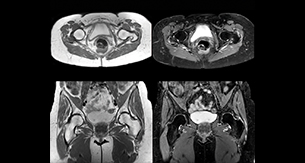

“For bone assessment near joints, mDIXON TSE provides the visualization and multiple contrasts to describe abnormalities within a limited number of acquisitions. Bone marrow signal abnormalities are common MRI findings that can represent various underlying causes, from normal variance to malignancy. So, it is important for us to notice and characterize these findings. With different contrasts, both with and without fat signal as mDIXON TSE efficiently provides, we can make a confident diagnosis.” “Other examples in bone are the signal description of a necrotic fragment in osteonecrosis, the signal description of tumoral matrix that has different components (necrosis, hemorrhage, cartilage, bone formation). These are all possible thanks to in-phase and water images from a single mDIXON acquisition.”

“In peripheral joints, mDIXON TSE imaging aids in diagnosing injuries in ligaments or tendons, for imaging degenerative and inflammatory pathologies such as osteoarthritis and rheumatologic disorders and for oncological exploration.” “For tendon and ligament assessment around knee, ankle, hip and elbow, mDIXON TSE contributes to diagnostic confidence thanks to having images both with and without fat suppression – and without time penalty. This is possible because 2-point mDIXON is faster than the common 3-point Dixon method. It can also increase efficiency as it helps avoid having to add scans during the exam.”